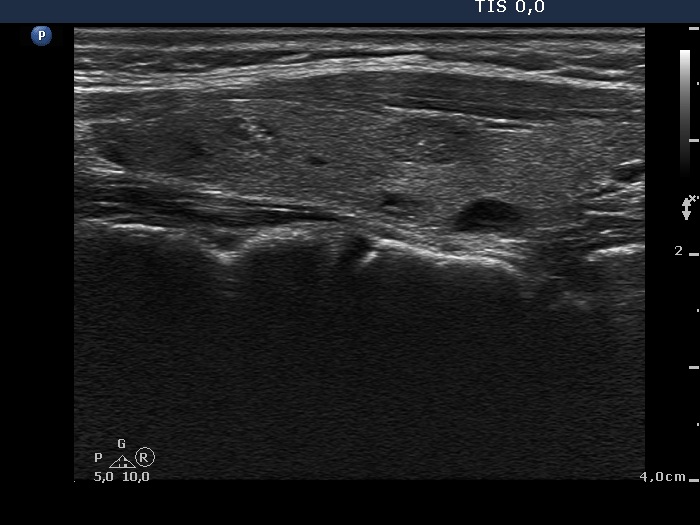

Ultrasonography. There was a moderately hypoechogenic nodule presenting halo sign and perinodular blood flow in the right while two smaller lesions in the left lobe. One of the latter displayed multiple microcalcifications.

The mass in the left side of the neck corresponded to a conglomerate of multiple lymph nodes. These were irregular in shape and presented cystic and necrotic areas. There was no hilum present. The lymph nodes were avascular.